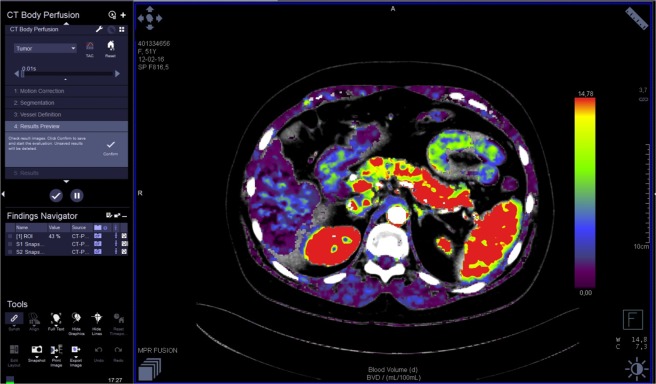

The images were analyzed by three radiologists (J.L.E. – reader 1, T.S.G. - reader 2, M.V. – reader 3) with 25, 16 and six years of experience in abdominal imaging, respectively. Each reader performed two reading sessions with at least a 24 h interval. The image data were processed on a workstation (Syngo.via®, Siemens) with commercial perfusion CT software (CT Body Perfusion, Siemens) based on the maximum slope model. Motion correction was performed by using a commercial non-rigid motion correction algorithm (Syngo®.via Body Perfusion, Siemens) to improve anatomical alignment. The following parameters were measured: blood flow (measured in mL/100 mL/min), blood volume (measured in mL/100 mL), time to peak (measured in seconds), and mean transit time (measured in seconds). Arterial input was measured by automatically placed ROI in the abdominal aorta. To obtain perfusion CT parameters, each radiologist manually drew three non-superposable circular ROI (between 1.0 and 2.0 cm²) in the head, three in the body and three in the tail of the pancreas to measure these parameters, avoiding visible vessels and ducts. The mean ROI value for each parameter in each part of the pancreas was considered for analysis. The parameters for the whole pancreas were calculated as the sum of the values of the pancreatic head, body and tail divided by three. An example of perfusion CT image processing is shown in Figs 1–3.

Figure 1.

Perfusion CT: image processing.